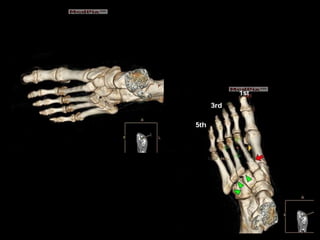

El METATARSO constade 5 pequeños huesos largos llamados METATARSIANOS. Se los diferencia contándolos de adentro hacia fuera así: 1°, 2°, 3°, 4° y 5° metatarsiano. Cada hueso se articula proximalmente con el tarso (ARTICULACION DE LISFRANC) y distalmente

Tipo A: desplazamientos de los 5 metatarsianos, con o sin fractura de la base del 2do metatarsiano. Se denominan homolaterales  Tipo B: están indemnes una o más articulaciones. Las B1 presentan desplazamiento medial. Las B2 presentan desplazamiento lateral y pueden afectar a la articulación entre la cuña y el primer metatarsiano.  Tipo C: son lesiones divergentes y pueden ser parciales (C1) o completas (C2). Son lesiones de alta energía y se asocian con

CLINICO  Radiografías AP, lateral y oblicua a 30º para evitar que pasen desapercibidas.  Es habitual la presencia de fracturas asociadas de la base del 2º metatarsiano así como marginales de la base del primero, por lo que es correcto hablar de fracturas-luxaciones de Lisfranc.

Reducción cerrada y estabilización percutánea con agujas de Kirschner. Para considerar la reducción correcta es necesario que la separación entre la base del 1er y el 2do metatarsianos sea como máximo de 3 a 4 mM.